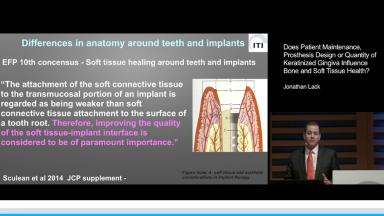

Based on a description of the differences between periodontal and peri-implant tissues, peri-implantitis and peri-implant mucositis are defined. Preventive measures to avoid peri-implant infection are listed, and treatment strategies are outlined, including cumulative interceptive supportive therapy (CIST) for peri-implant mucositis and peri-implantitis. The available and increasing evidence for the importance of a zone of keratinized peri-implant mucosa to preserve healthy peri-implant tissues long-term is presented. Finally, the lecturer underlines the importance of designing prosthetic superstructures with adequate access for proper diagnostics and home care for the patient.

- describe the anatomic differences between gingiva and peri-implant mucosa

- recognize that lack of keratinized mucosa may increase the risk of biologic complications